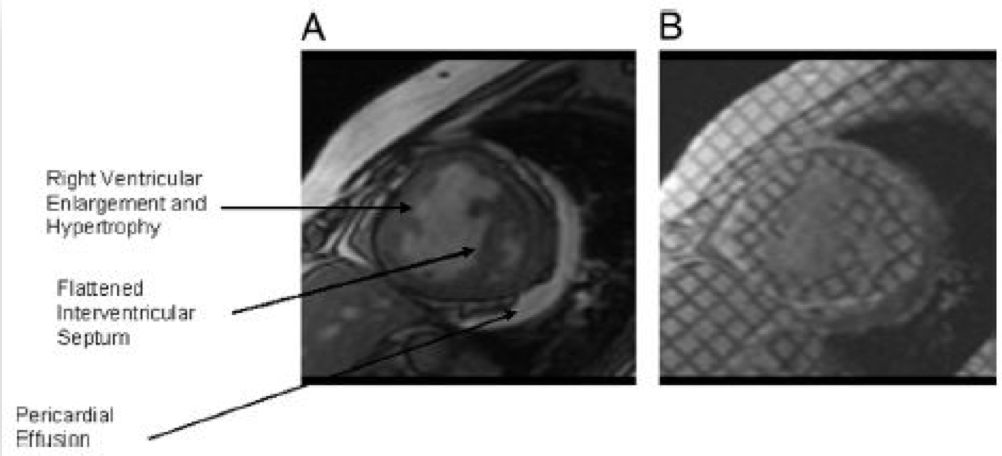

• MR

➤ 右心衰竭的评估:心脏核磁

• 心脏磁共振检查是评价右心结构、功能的金标准,右心导管是评估肺动脉压、右室舒张末压的金标准,但临床最常用的检查为心脏超声检查;